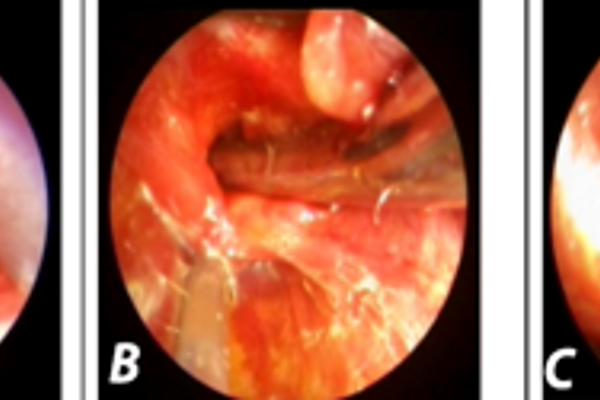

Management of benign oesophageal strictures